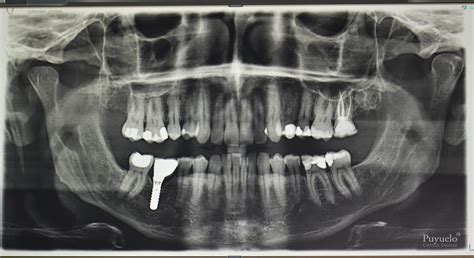

Implantología dental

Gracias a la ortopantomografía somos capaces de planificar tratamientos de implantes dentales mucho más precisos y seguros. La radiografía nos aporta información sobre el hueso dental, su cantidad y la calidad del mismo. Teniendo esto en cuenta recurrimos a un tipo de implantes o a otro. La colocación de implantes dentales requiere precisión y experiencia, además del uso de materiales de alta calidad. Gracias a nuestras pruebas radiográficas somos capaces de predecir el lugar exacto en el que se debe de colocar el implante dental, con el fin de evitar daños en los nervios de la boca.

Aunque también la utilizamos de forma complementaria en implantología y extracción de las piezas cordales (las últimas muelas que nos salen), en algunas clínicas se utiliza CBCT, el escaneado de la boca en 3D para hacer la planificación de ambos tratamientos.